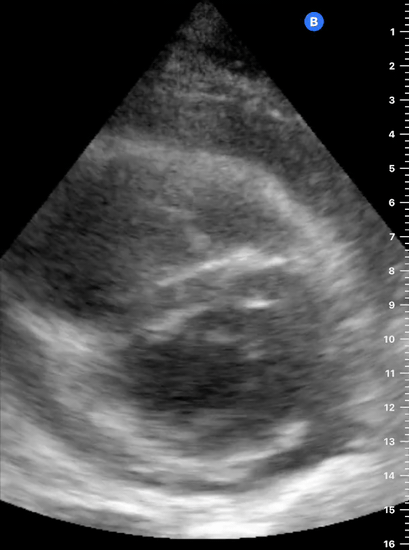

Effusion: is there a pericardial or pleural effusion?

Pericardial effusion is a continuum and can potentially evolve into haemodynamic collapse. Tamponade physiology is detectable earlier with ultrasound than with traditional physical examination, and it has been demonstrated that PoCUS improves mortality in penetrating cardiac trauma. Timely and accurate diagnosis is, therefore, vital.

THE VIEWS

The subxiphoid view is the most reliable for detecting pericardial effusion. Still, it is ideal to obtain different views not to miss a focal effusion as small amounts of fluid can lead to tamponade physiology. Tamponade does not link strictly to the size of the effusion, but correlates more with the speed of onset, causes, and haemodynamic effects.

PITFALLS & PLEURAL EFFUSIONS

A common error is to confuse a pericardial fat pad with effusion. Fatty tissue has a heterogeneous echotexture, moving in coordination with the myocardium, and it cannot be tracked around the heart, especially posteriorly and to the apex. Another pitfall is misinterpreting a pleural effusion as a pericardial effusion. However, they can be differentiated by their relationship to the descending aorta. Pericardial effusion may be seen between the aorta and the LV free wall, whereas pleural effusions are posterior to the descending aorta. Lastly, other causes, namely hypovolaemia and large pleural effusions, can cause RA and RV collapse.

CARDIAC TAMPONADE

Progressively rising pressure translates into evolving tamponade, and this accompanies a series of ultrasound findings:

Initially, the RA collapses during ventricular systole (closed AV valves).

Followed by RV collapse in ventricular diastole (open AV valves).

Ultimately leading to LV collapse.

In addition, the presence of a non-collapsible, plethoric IVC is one of the most sensitive signs of tamponade, and a finding easy to visualise. Conversely, a pericardial effusion in a haemodynamically stable patient with a collapsible IVC is unlikely to represent tamponade.

Chamber collapse can be assessed in M-mode, where the collapsing RV is seen as a notch that takes place right after the mitral valve opening and before its closure (during diastole).